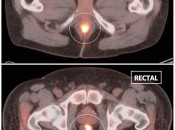

Hemorrhoidal Inflammation:

Focal intense uptake in the ano-rectal region is a very common finding. It is considered normal in the absence of an associated soft tissue abnormality. It is often attributed to hemorrhoidal inflammation.

Be careful to not confuse ano-rectal uptake (typically representing hemorrhoidal inflammation) with rectal uptake (often malignancy).

Metformin:

This very popular medication is notorious for causing extensive and extremely intense bowel uptake (colon > small bowel). As this uptake can occasionally limit interpretation, we ask our patients to discontinue Metformin 24-hours prior to their exam.